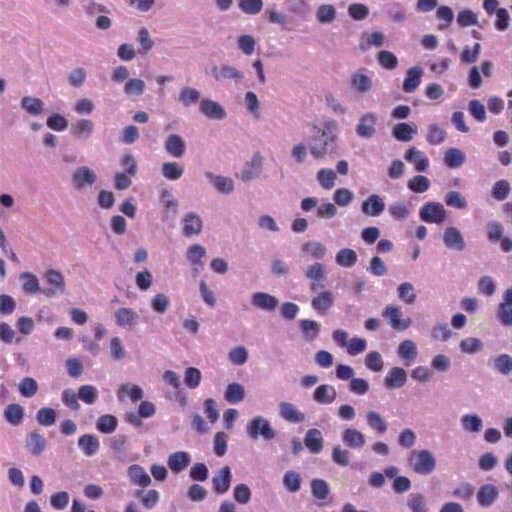

The lymphoid tissue exhibits a dense infiltrate of small lymphocytes and interspersed atypical cells with prominent nucleoli, suggesting a lymphoproliferative disorder. Lymphoma cells are effaced without normal follicular architecture, fibrous stroma, collagen, and necrosis. Lymphocytes show abundant cytoplasm and smaller cells chromatin chrom. Findings hint at a lymphoproliferative disorder, possibly Hashimoto's in the context of a lymph node mass in a 60-year-ac male with ayminal mass, possible Reed-Sternberg cells, macrophages, autoimmunity, or reactive re blast forms. The lungs are intact, with some signs of atypia. Diagnosis requires more immunohistochemical tests, stain imaging data to differentiate from other reactive or CDic degenerative changes. The findings suggest a lymphoproliferative disorder, possibly reactive lymphocyte or histiytosis.